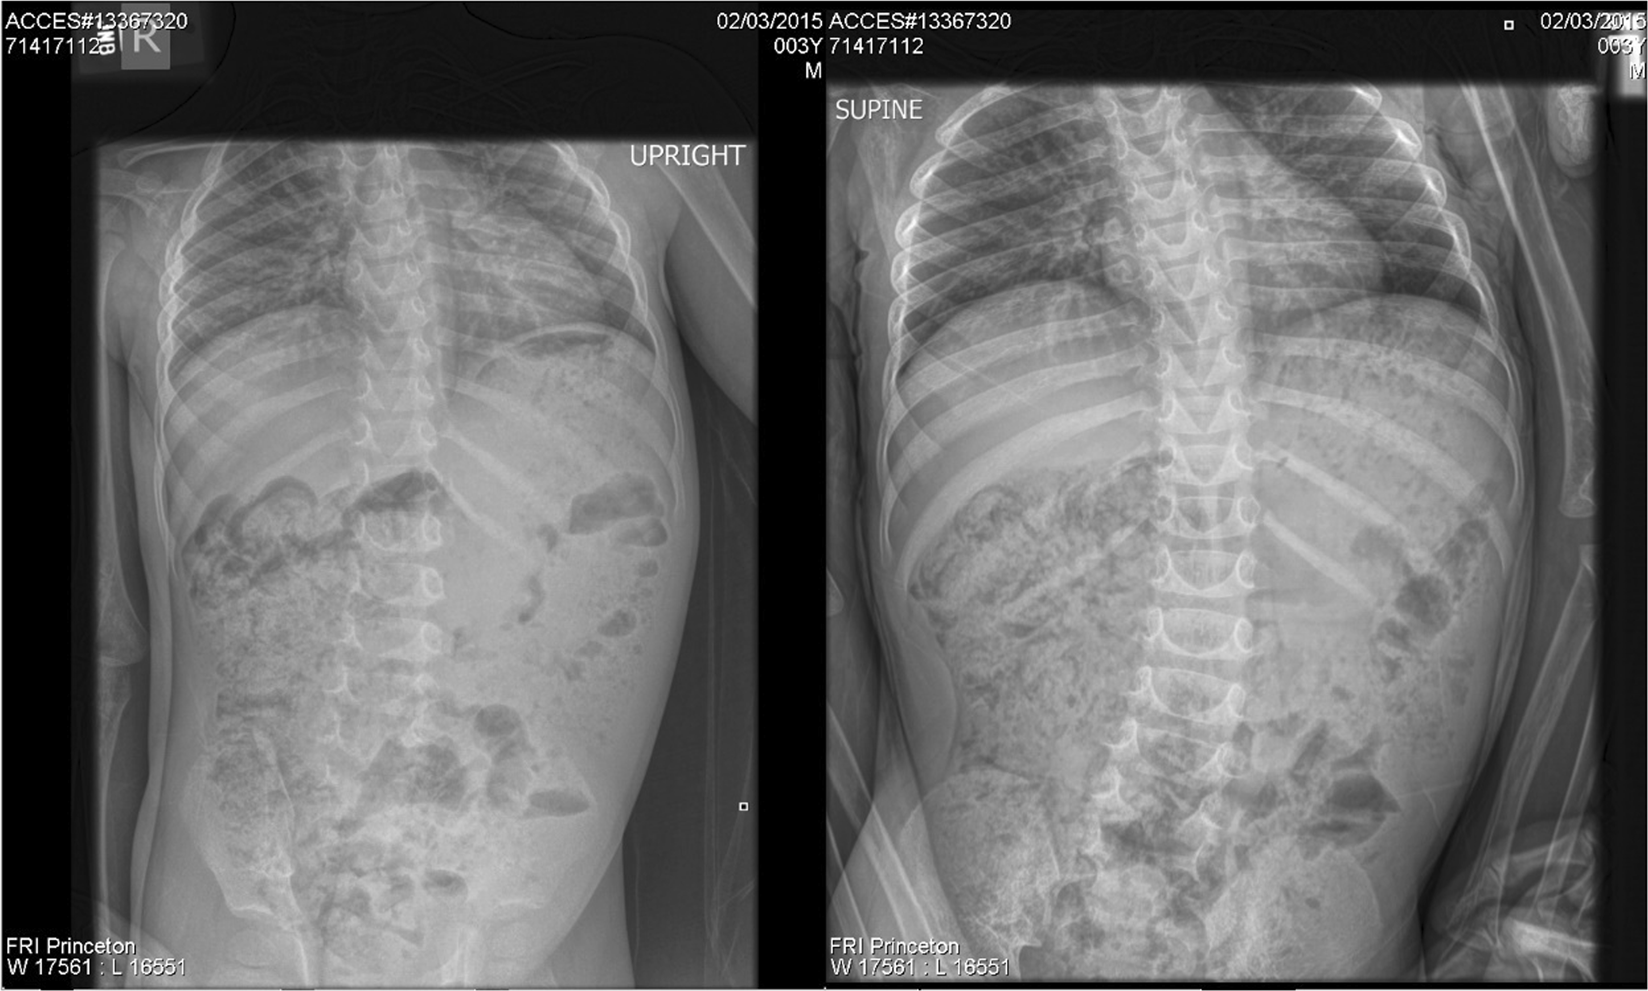

One or more conditions can cause fecal incontinence such as. For children older than age 4 the most common cause of fecal incontinence is constipation with a large amount of stool in the rectum. Causes of bowel incontinence.